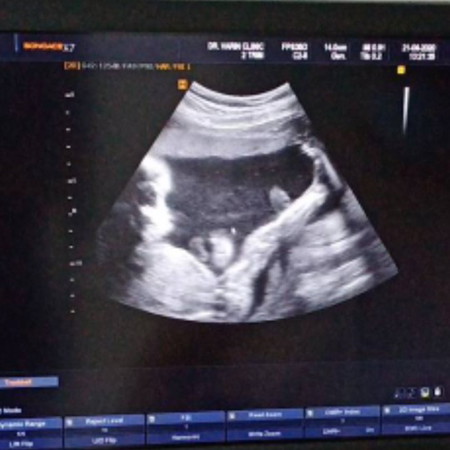

โชว์ภาพอัลตร้าซาวด์ลูกๆทีมตุลาหน่อยคร่าา เด็กหญิง อายุครรภ์ 21w4d โชว์เตะขาสูงไปเล้ยย

น้องดูเเข็งเเรงมากเลยค่ะคุณเเม่🥰 บ้านนี้ทีมตุลาเหมือนกันค่ะเเต่ยังไม่ได้ไปซาวด์ครั้งล่าสุดเลย รอหมอนัดค่ะ ยังไม่รู้เพศน้องเลย55 ดูเเลบำรุงตัวเองเยอะๆนะคะ💝